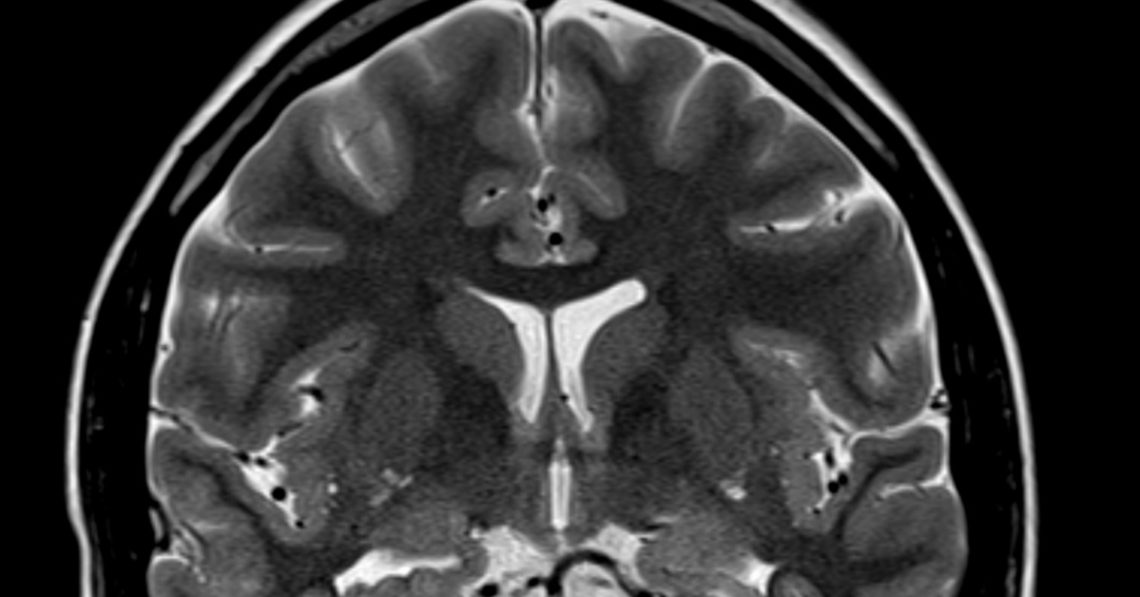

Researchers publishing in PLOS Biology found that older adults who have played music for decades have brains that function more like those of someone half their age, at least when it comes to understanding speech in loud environments. In brain scans, they showed cleaner, more focused activity while listening to spoken syllables buried in background noise. Their brains weren’t scrambling. They already knew what to do.

And this wasn’t just about volume or clarity. The musicians’ brains didn’t just respond better; they were organized in the same layout seen in younger adults. Non-musicians showed shifted activity, like their brains were improvising. The musicians stuck to the original arrangement and got better results.